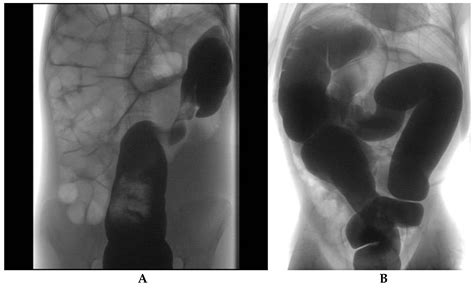

The Birdbeak Sign is a distinctive radiographic appearance seen on abdominal X-rays or CT scans. It is characterized by a tapered, beak-like appearance of the sigmoid colon, which indicates a twist or volvulus. This sign is crucial because it helps radiologists and gastroenterologists identify the presence of a sigmoid volvulus, which is a medical emergency requiring immediate intervention.

Interpreting the Birdbeak Sign During Flexible Sigmoidoscopy

During a flexible sigmoidoscopy, the presence of a Birdbeak Sign can be confirmed by visualizing the twisted sigmoid colon. The sigmoidoscope allows for a direct view of the colon, enabling the gastroenterologist to assess the extent of the twist and the condition of the colonic mucosa. This direct visualization is crucial for confirming the diagnosis and planning the appropriate management strategy.